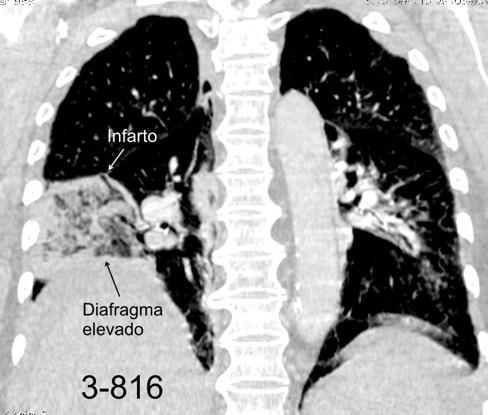

25. ELEVACIÓN UNILATERAL. TEP

Tromboembolismo pulmonar Diafragma elevado 20%